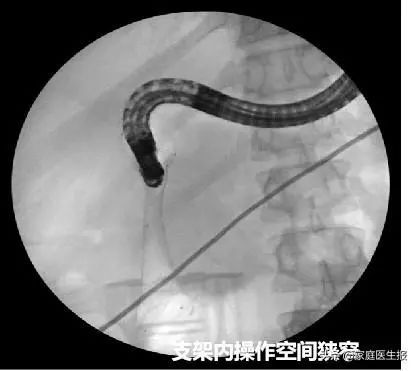

内镜虽然可顺利通过十二指肠狭窄处,可是又遇到了新的难题:支架挡住了十二指肠乳头,暴露乳头及尝试ERCP插管困难。熊光苏带领ERCP团队耐心调整内镜视野,在金属支架网孔中寻找到乳头。经预切开、插管、造影、胆道扩张、支架置入等一系列操作,最终成功引流出黑色胆汁。

熊光苏又补充道:“这例患者还算比较顺利的,我们放置十二指肠支架后能顺利到达降部。以往有的患者因为压迫严重,放置十二指肠支架后内镜还是无法通过,往往需要临时再次球囊扩张保证内镜通行。支架置入的同时,往往又会影响乳头的观察,因为操作空间和视野狭小,寻找乳头及后续ERCP操作非常不顺手。部分情况下,为了保证手术的顺利进行,甚至需要拔除支架再进行后续操作,这些都是对手术时间和技能的巨大挑战。”